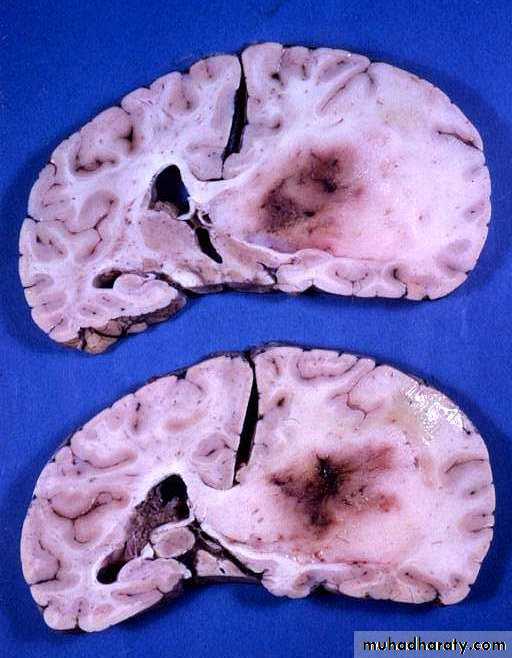

Metastatic Brain Tumours

Metastatic Brain Tumours Pre contrast CT

Metastatic Brain Tumours Post contrast CT